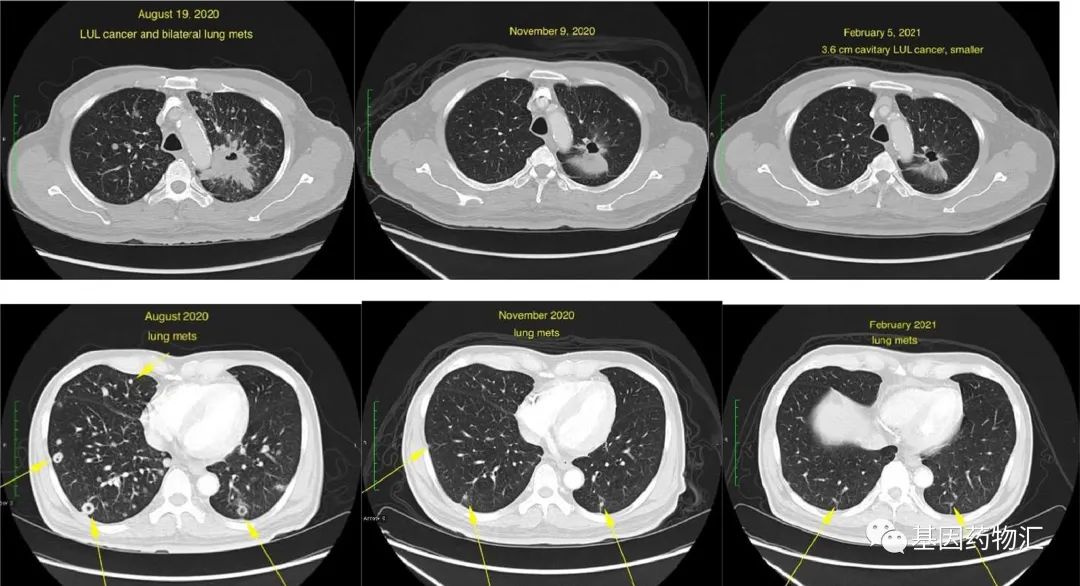

用药仅6周,患者的CT影像学表现就已经有了非常明显的改善。根据报告,患者肺部的小病灶,从最初检查时的超过100个,减少到了25个,纵隔淋巴结转移病灶以及肝脏的转移病灶也在缩小,癌胚抗原水平明显降低。

最后,让我们一起来看一看整个确诊与治疗过程当中患者影像学上的变化。下方图像由左至右分别为患者接受拉罗替尼治疗前、接受拉罗替尼治疗6周后、接受拉罗替尼治疗20周后的原发左上叶肺腺癌(上方三图)和纵隔转移病灶(下方三图)的影像。